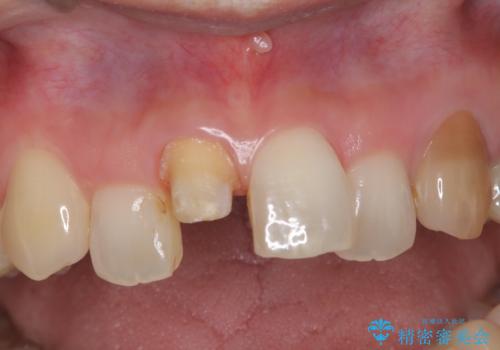

【オールセラミック】前歯の色を変えたい。

- 前歯の色が変色してきたことを主訴に来院されました。

根管治療から被せものまで治療を行いました。